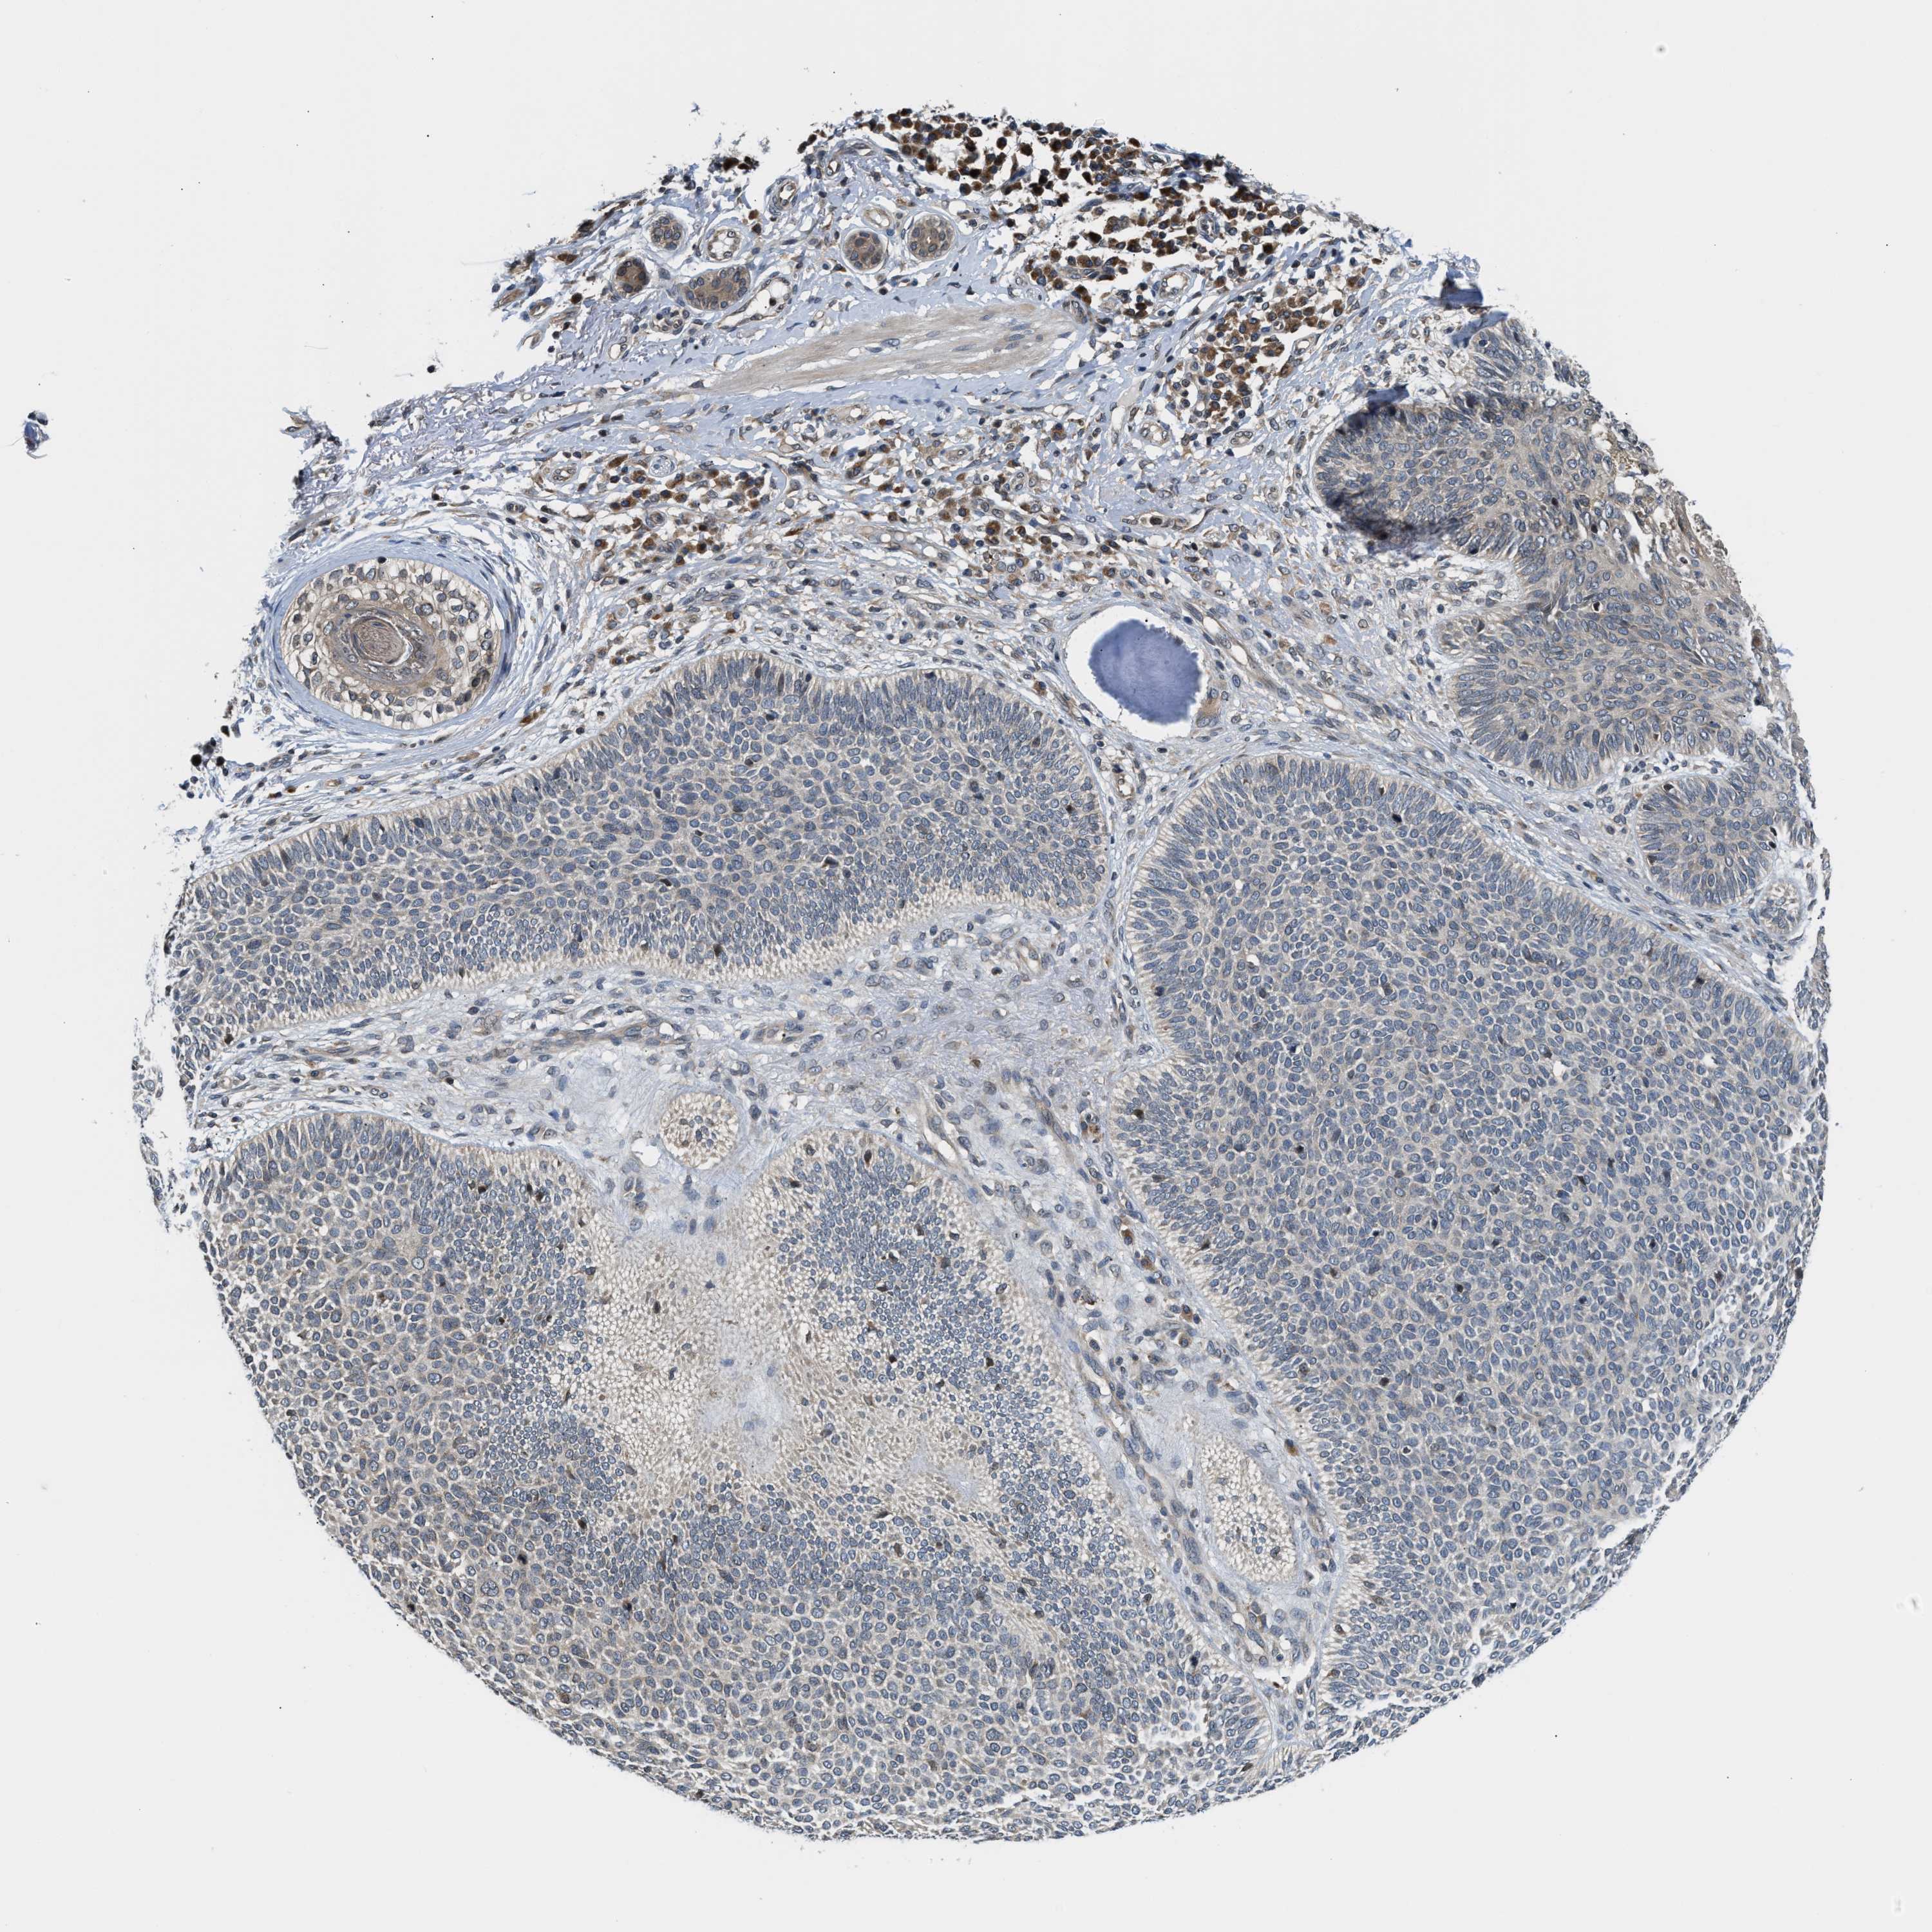

SKIN CANCER - Protein expressioni

A mouse-over function shows sample information and annotation data. Click on an image to view it in a full screen mode. Samples can be filtered based on level of antibody staining by selecting one or several of the following categories: high, medium, low and not detected. The assay and annotation is described here.

Antibody stainingi

Antibody staining in the annotated cell types in the current human tissue is reported as not detected, low, medium, or high, based on conventional immunohistochemistry profiling in selected tissues. This score is based on the combination of the staining intensity and fraction of stained cells.

Each image is clickable and will lead to virtual microscopy that enables deeper exploration of all samples and also displays staining intensity scores, fraction scores and subcellular localization as well as patient and tissue information for each sample.

Antibody HPA026303

Antibody CAB020822

Basal cell carcinoma